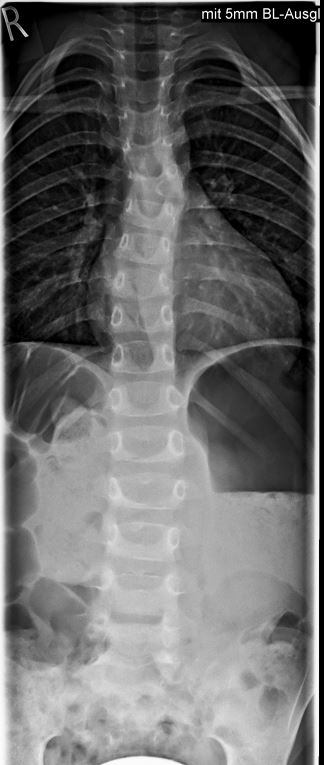

Bei meiner 4 Jährigen Tochter wurde vor einigen Tagen ein Halbwirbel im 6 BWS festgestellt.

Dadurch natürlich eine Koliose leider haben wir keine Angaben wie hoch die Gradzahl ist.

Also für mich wäre das definitiv noch keine OP Indikation. Ich würde versuchen die Verschlechterung mit einem Korsett aufzuhalten. Wenn alles so bleibt werden mit hoher Wahrscheinlichkeit keine Probleme auftreten. Aufgrund der Höhe der Krümmung bei T6 geht sicher nur ein Nachtkorsett. Das sollte aber ausreichen. Sollte die Krümmung im Verlauf der Jahre doch zunehmen, kann man die Op immer noch durchführen. In der Regel kann der Verlauf jedoch gestoppt werden.

PS. Hier mal die RÖ-Bilder

RB.JPG

RB.JPG (41.84 KiB) 7695 mal betrachtet